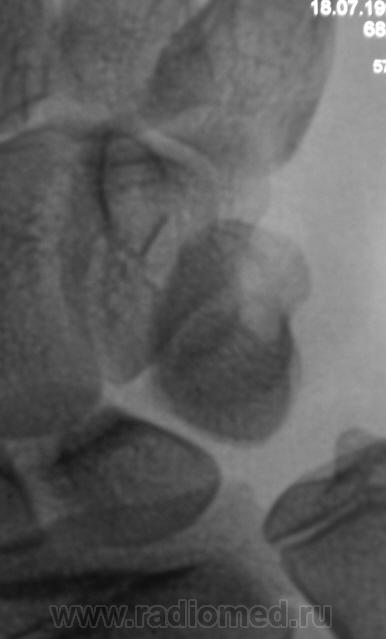

Смущает перестройка структуры костной ткани, помечено стрелками.

111._Struktura..JPG112._Struktura..JPG

Похоже на кисты (здесь - врождённые)

А может ГКО?